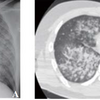

・この時点で胸部単純レントゲン撮影がされた

右上葉に浸潤影を認める

・外科的気道確保がされた翌日、CTが撮影された

気管支狭窄(矢印)と、その周囲の軟部組織腫脹や複数のリンパ節腫脹(矢頭)

T4-6レベルでの気管狭窄が強い